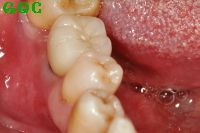

▼抜歯後![]() |

▼被せ歯装着![]() |

単に歯を入れるというだけでなく、噛み合わせについてもきちんと計算されつくしていると感じました。ブリッジや入れ歯ではこうはならないと思います。